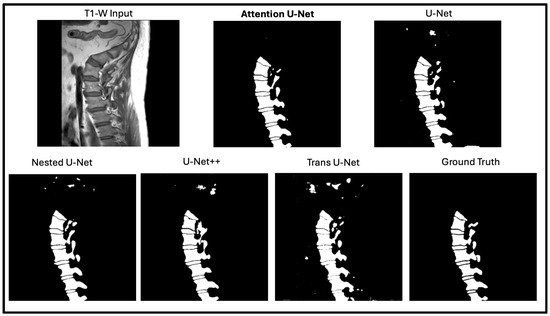

In this portion of the results, we focus on manually assessing the segmentation quality of the network outputs (Figure 5). While quantitative metrics like DICE and SSIM capture the quantitative performance of the segmentation models, we still wanted to see how these outputs are reflected in real time. DICE and SSIM might fail to highlight some subtle boundary mismatches or some issues in segmentation of complex structures. By incorporating qualitative observations, we aim to provide a more comprehensive evaluation of the network’s performance. Figure 6 shows the output of the model against the four other state-of-the-art U-Net networks. The attention U-Net is bolded as the top algorithm. Two algorithms that were close with respect to DICE, SSIM, and the radiologist reports were the Attention U-Net and the Nested U-Net. We thought it would be best if we showed the visualization to demonstrate the differences. Figure 7 highlights the difference and clearly shows the addition artifacts created by the Nested U-Net. While most of the segmentation is similar, the edges are not as clearly defined. The red boxes show the zoomed in portion of both, further demonstrating the difference between the two.

Figure 6. Segmentation comparison across five U-Net variants on a lumbar T1-weighted spinal MRI. The Attention U-Net produces the most anatomically accurate result, closely matching the ground truth with clear vertebral boundaries. Other models show minor artifacts or boundary inconsistencies, highlighting the Attention U-Net’s stronger feature localization and structural precision.